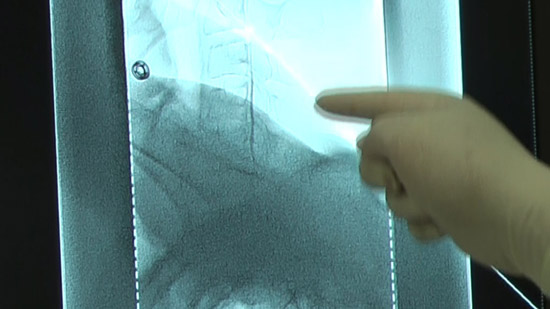

(4)Conduct an epidural puncture by the resistance loss method, checking with the image on the radioscopy screen.

※Inject the contrast medium and check it again. Capture a confirmation image at the same time.

Check with the image on the radioscopy screen.

Check subjective physical condition of patients after 10 cc infusion and capture a projectional image.

Capture projectional images at the end of infusion.